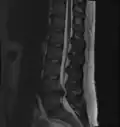

MRI scan of large herniation (on the right) of the disc between L4 and L5 vertebrae

MRI scan of large herniation (on the right) of the disc between L4 and L5 vertebrae -

A rather severe herniation of the L4–L5 disc

A rather severe herniation of the L4–L5 disc -

Example of a herniated disc at L5–S1 in the lumbar spine

Example of a herniated disc at L5–S1 in the lumbar spine